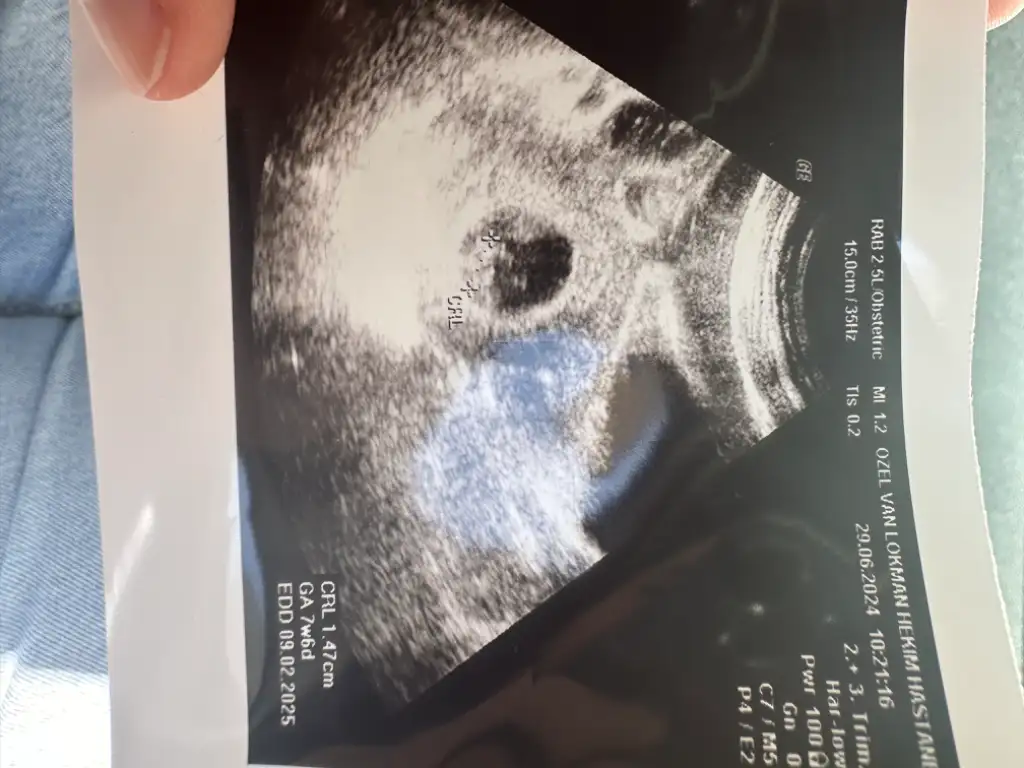

eğer o bebekse keseye göre kücük görünüyor. doktorunuz en iyisini bilir ama benim 6+6da hem bebek hem de kalp atısı görünmüştü.Oradaki beyaz nokta bebek görüntüsü işte geç döllenme falan oluyor ya umut ediyorum işte

bu iki ultrasonda da crl bebek boyutu ise aynı görünüyor sadece ölçek farklı yani biri birinden daha büyük değil yani keseye göre küçük demek yanlış ve pervasızca olurBaşka yorumu olan yok mu tek kişi mi cevap verdi

pervasızca?? jfjfj konu sahibinin ultrason kağıdındaki ölçümler karışık olduğu için ona dikkat etmedim. fark ettiyseniz bazı ölçümler 35.hafta falan görünüyor. bir hata olmus olabilir bilmiyorum. yani kağıttaki crl konu sahibinin bebeğinin ölçümümü açık değilbu iki ultrasonda da crl bebek boyutu ise aynı görünüyor sadece ölçek farklı yani biri birinden daha büyük değil yani keseye göre küçük demek yanlış ve pervasızca olur

Amin Allah razı olsun inşallah Allah isteyen herkese sağlıklı hayırlı evlat nasip etsin inşallah. Kese var küçük ama sanırım geç döllenme dedi bebek ve kalp sesi için de 20 gün sonra gel dedi bir dahaki muayenese duyarız dedi o zaman kadar sabredebilcek miyim bilmiyorim. Ama devlet hastanesine gitmeye de korkuyorim açıkçası kötu birşey duymak istemiyorumAyy inşallah kucağınıza almayı nasip etsin inşallahdoktor ne diyor pekı kesesi falan düzgün müymüş peki az çok birşey diyorlar çünkü kusıra bakmayı böyle soruyorum ama içim çok acıyor benim bir oğlum var en azından onunla avutuyorum kendi mi ama oda çok kardeş istiyor bu son bebeğimi sanıyorki yaramazlık yaptım ondan mı öldü benim kardeşim falan diyor kardeş istiyor soruyor karnında bebek mi var fakan o böyle şeyler konuştukça ben kendi mi daha kötü hissediyorum aglıyorum hep geceleri

Ben aydın söke'de yaşıyorum söke'de doktor varda yok malesef en son tavsiye üzerine kuşadasında bir doktor gittim o doktor çok iyiydi ya kürtaj mı da onda oldum benimle o kadar ilgilendi ki anlatamam her doktor bir değil malesef iki doktorda devlette çalışıyor mesela benim oğluma da öldü imza at aldıralım demişlerdi atmadım imzayı gene başka doktora gittim öyle birşey yok dedi kalbinde üfürük vardı sadece 2 yaşına gelince kapanır dediler öylede oldu şuan oğlum 5 yaşında okula gidiyor doktor inanınp alsaydım hiç çocuğum olamicaktıAmin Allah razı olsun inşallah Allah isteyen herkese sağlıklı hayırlı evlat nasip etsin inşallah. Kese var küçük ama sanırım geç döllenme dedi bebek ve kalp sesi için de 20 gün sonra gel dedi bir dahaki muayenese duyarız dedi o zaman kadar sabredebilcek miyim bilmiyorim. Ama devlet hastanesine gitmeye de korkuyorim açıkçası kötu birşey duymak istemiyorum